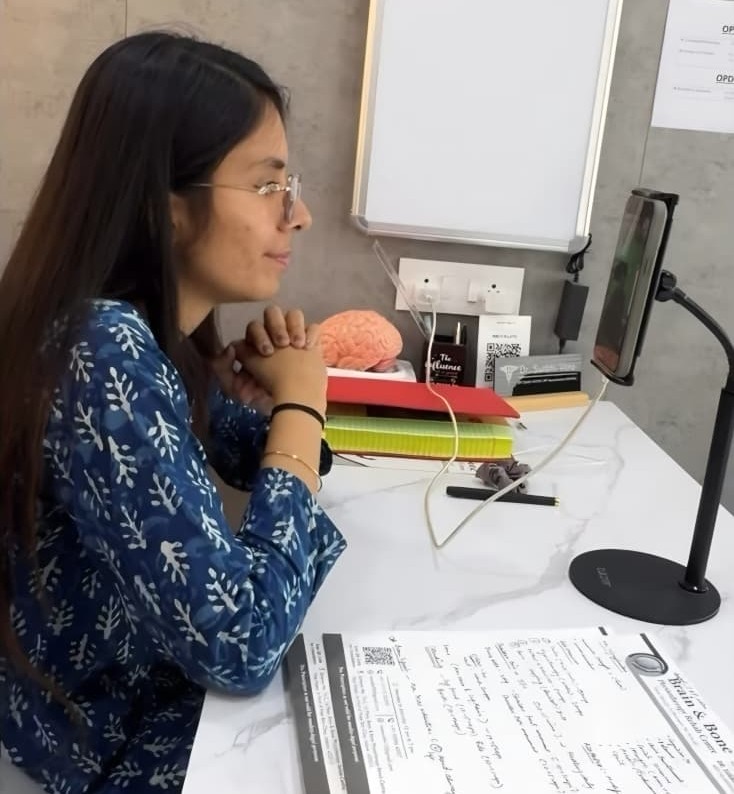

Evidence-Based Physiotherapy Care By Experts

We offer specialized treatments for a wide range of conditions, focusing on personalized programs to restore movement and improve quality of life. Our team uses the latest rehabilitation protocols to ensure the best outcomes for our patients in Indore.